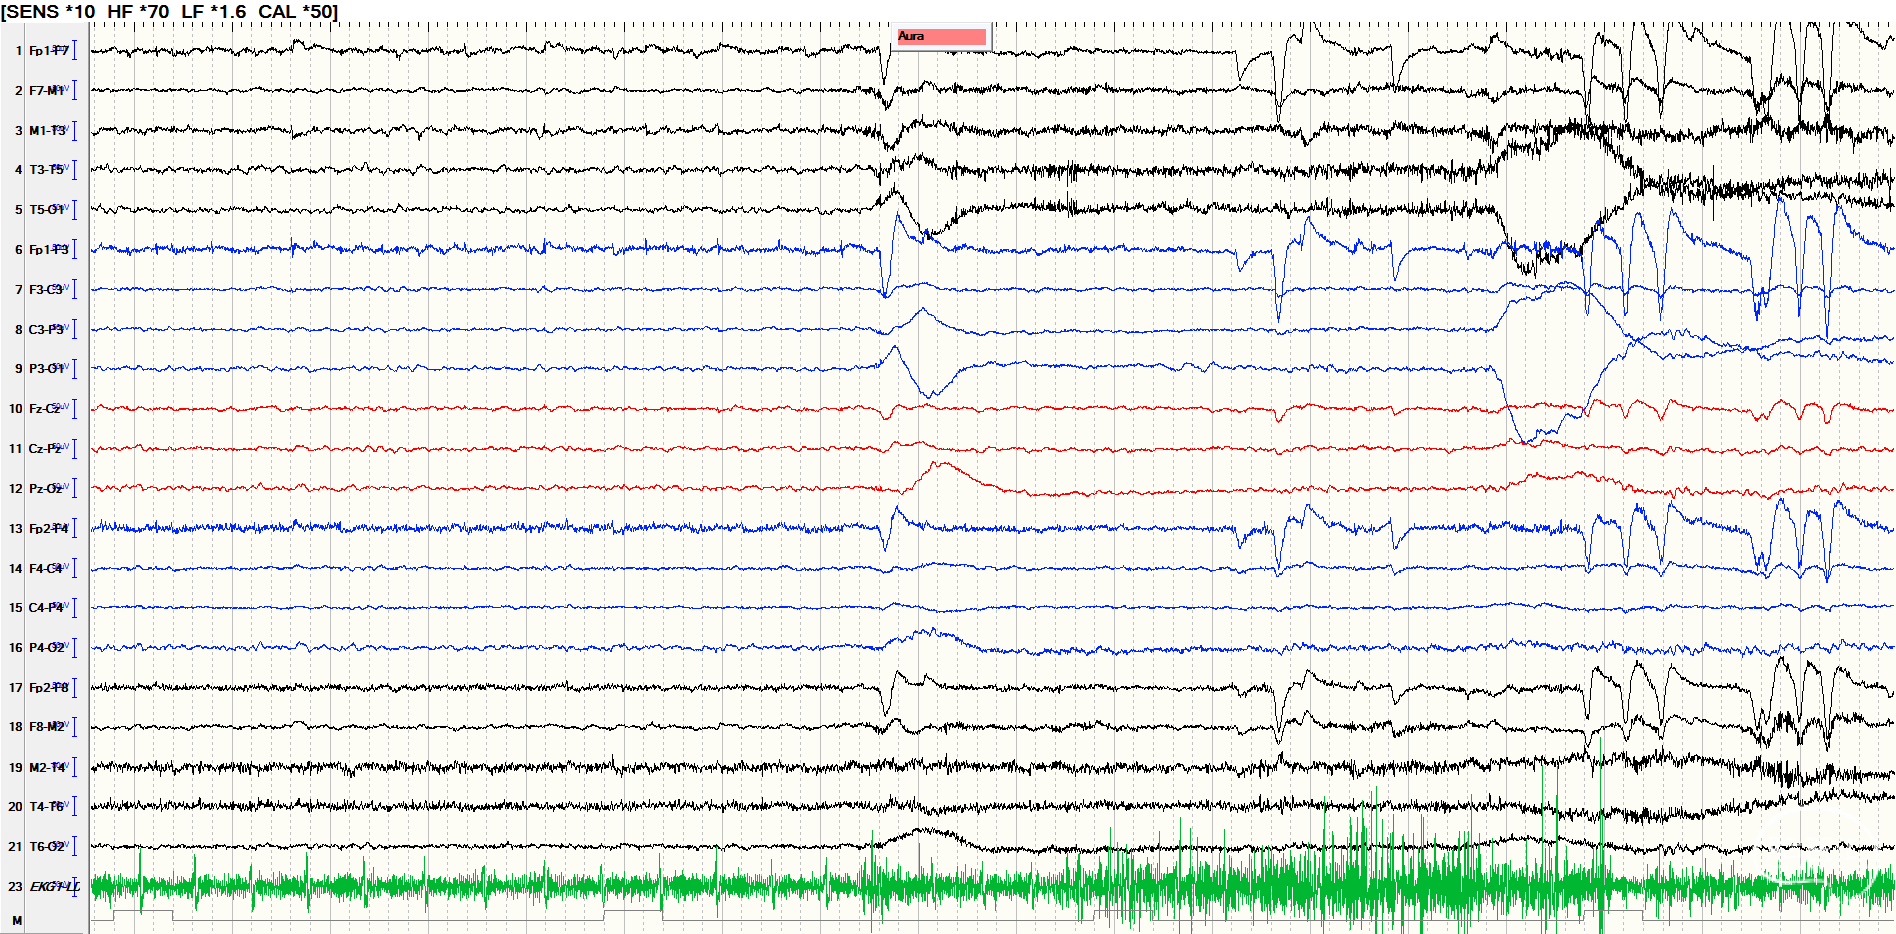

后转求至我院,详细询问病史并完善查体后发现患者脐下、右侧股外侧2*3cm色素脱失斑(图1)。完善脑电图检查提示间歇期放电脑区性,左后头著(图2),4天共监测到3次临床发作,表现为先兆(右肩重压过电感)→强直发作(累及右上肢)→阵挛发作(右上肢远端),同步脑电图示弥漫性电压低减,无侧向性(图3)。头颅MRI提示颅内多发异常信号(图4)。头颅CT提示颅内有钙化灶(图5)。头颅PET见左侧楔前叶低代谢(图6)。

图3.发作期脑电图示弥漫性电压低减,无侧向性。

![]()